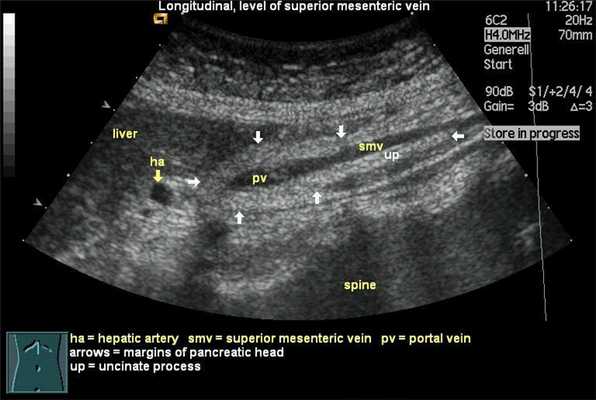

Поджелудочная железа лежит на задней брюшной стенке с головой в виде буквы С исходящей из двенадцатиперстной кишки. Тело и хвост простираются наклонно вверх влево, хвост поджелудочной железы лежит в селезеночно-ренальной связке рядом с селезенкой и верхним полюсом левой почки. Головка поджелудочной железы имеет крючковидный отросток, который распространяется позади нижней части верхней брыжеечной вены в начале воротной вены. Крючковидный отросток распространяется ниже основного тела поджелудочной железы, поэтому важно при ультразвуковом исследовании сканировать всю протяженность поджелудочной железы, иначе может быть пропущен рак крючковидного отростка.

Поджелудочная железа лежит в переднем параренальном пространстве. Головка лежит в изгибе петли двенадцатиперстной кишки с нижней полой веной и правыми почечными сосудами, лежащими сзади. Общий желчный проток получает главный проток поджелудочной железы, когда он проходит через головку поджелудочной железы, а затем дренируется во вторую часть двенадцатиперстной кишки в ампуле Фатера. Гастродуоденальная артерия может быть видна спереди в области поджелудочной железы и шейке. Головка поджелудочной железы - самая выпуклая часть железы, которая затем сужается в области шейки. Объединение верхних брыжеечных и селезеночных вен, образующих портальную вену сзади, отмечает анатомическое положение шейки поджелудочной железы. Привратник и гастродуоденальная артерия расположены спереди. Малая кривизна желудка лежит впереди тела поджелудочной железы, в то время как селезеночная вена проходит вдоль ее задней верхней поверхности. Хвост поджелудочной железы связан с селезенкой, левым надпочечником и верхним полюсом левой почки.